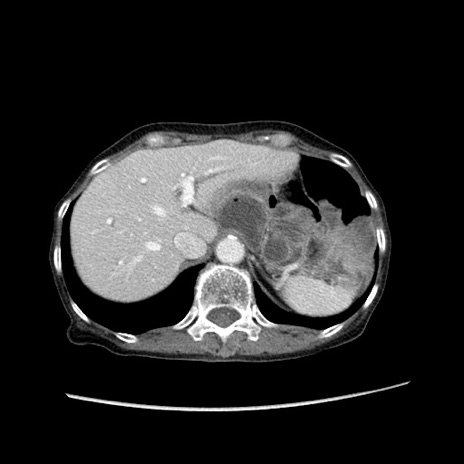

冠状断像

【症例】80歳代女性

【主訴】胸のつかえ感

【現病歴】約9時間前に食後から胸のつかえた感じあり、嘔吐あり、来院。

【既往歴】胃癌(全摘)、胆摘、虫垂炎

【身体所見】心窩部に圧痛あり、反跳痛なし。

【データ】WBC 5700、CRP 0.05